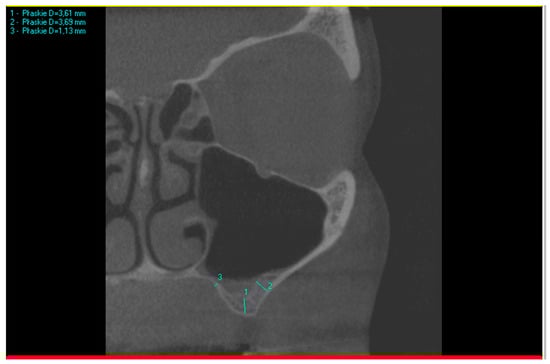

The three measurement points on the CBCT scans are illustrated in Figure 1.

Figure 1.

Example of three measurements taken on a CBCT scan. Measurement no. 1 is sub-sinus residual bone height, measurement no. 2 is the thickness of the lateral wall, and measurement no. 3 is the thickness of the palatal wall.

When comparing the thickness of the lateral and palatal walls in patients who needed direct sinus floor augmentation, if the difference between the two wall measurements was less than 100% of the smaller measurement, their thickness was considered comparable. In the example shown in Figure 1, measurement no. 1 (3.61 mm) presents insufficient bone height for implant placement. Based on that, the following subsequent measurements were taken: no. 2 (3.69 mm) and 3 (1.13 mm). The difference between the thicker wall (3.69 mm) and the thinner wall (1.13 mm) was 2.56 mm, which is more than 1.13 mm (100% of the thinner wall). In this case, the walls cannot be described as of a similar thickness.